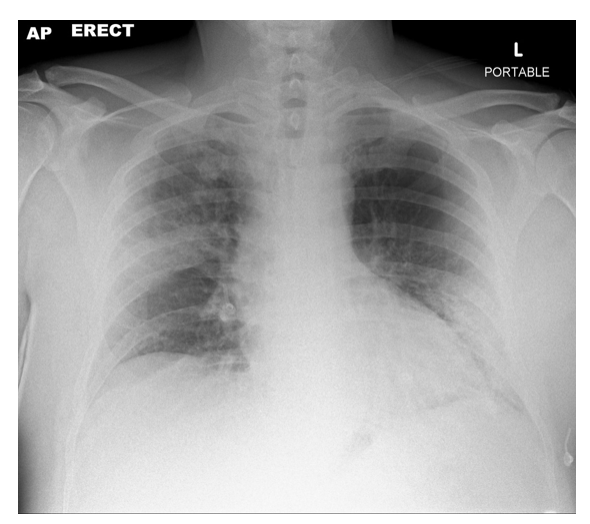

앞쪽은 anterior 라고 하고, 뒷쪽은 posterior라고 해요. anatomical position에서 배꼽은 anterior에 있고, 손등은 posterior에 있습니다. 엑스레이를 촬영하면 우리 몸을 관통해서 찍기 때문에 좌우를 구별하기 어렵습니다. 사진만 봐서는 앞에서 찍었는지 뒤에서 찍었는지 모르기 때문에, 좌우구별도 불가능합니다. 그래서, 좌우와 앞에서 찍었는지 뒤에서 찍었는지를 꼭 기록해 놓습니다.

그래서 엑스레이 필름을 보면 이렇게 좌우를 나타내는 L 혹은 R 이있습니다. 그 외에 왼쪽 상단에 보면 AP라는 말이 있죠? 이게 앞에서 뒤를 향해 찍었다는 말이예요. anterior → posterior를 AP로 쓴 것입니다. 옆에 erect란 말은 서서 찍었다는 이야기 입니다.